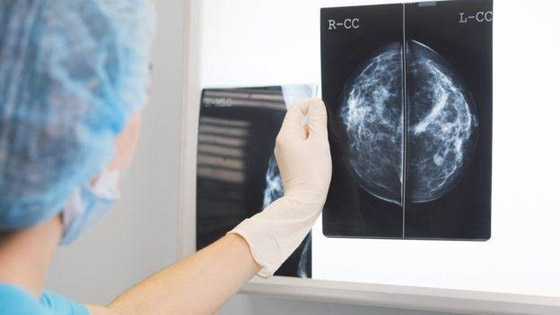

ذكر باحثون في الولايات المتحدة وبريطانيا أن نظاماً للذكاء الاصطناعي بغوغل أثبت دقة مماثلة لدقة خبراء الأشعة في اكتشاف النساء اللاتي أصبن بـ سرطان الثدي، استناداً إلى تصوير الثدي بالأشعة السينية وأظهر كفاءة في تقليص الأخطاء. وهذه الدراسة، التي نشرت في دورية نيتشر، هي أحدث بحث يظهر أن الذكاء الاصطناعي لديه إمكانية تحسين دقة الفحص لسرطان الثدي، الذي يصيب امرأة من كل 8 نساء في العالم.

وتقول الجمعية الأميركية للسرطان إن نسبة الخطأ لدى أطباء الأشعة في تشخيص سرطان الثدي من خلال التصوير بـ الأشعة السينية تبلغ 20 بالمئة، وإن نصف النساء اللائي خضعن للفحص خلال فترة 10 سنوات جرى خطأ تشخيص إصابتهن بالمرض.